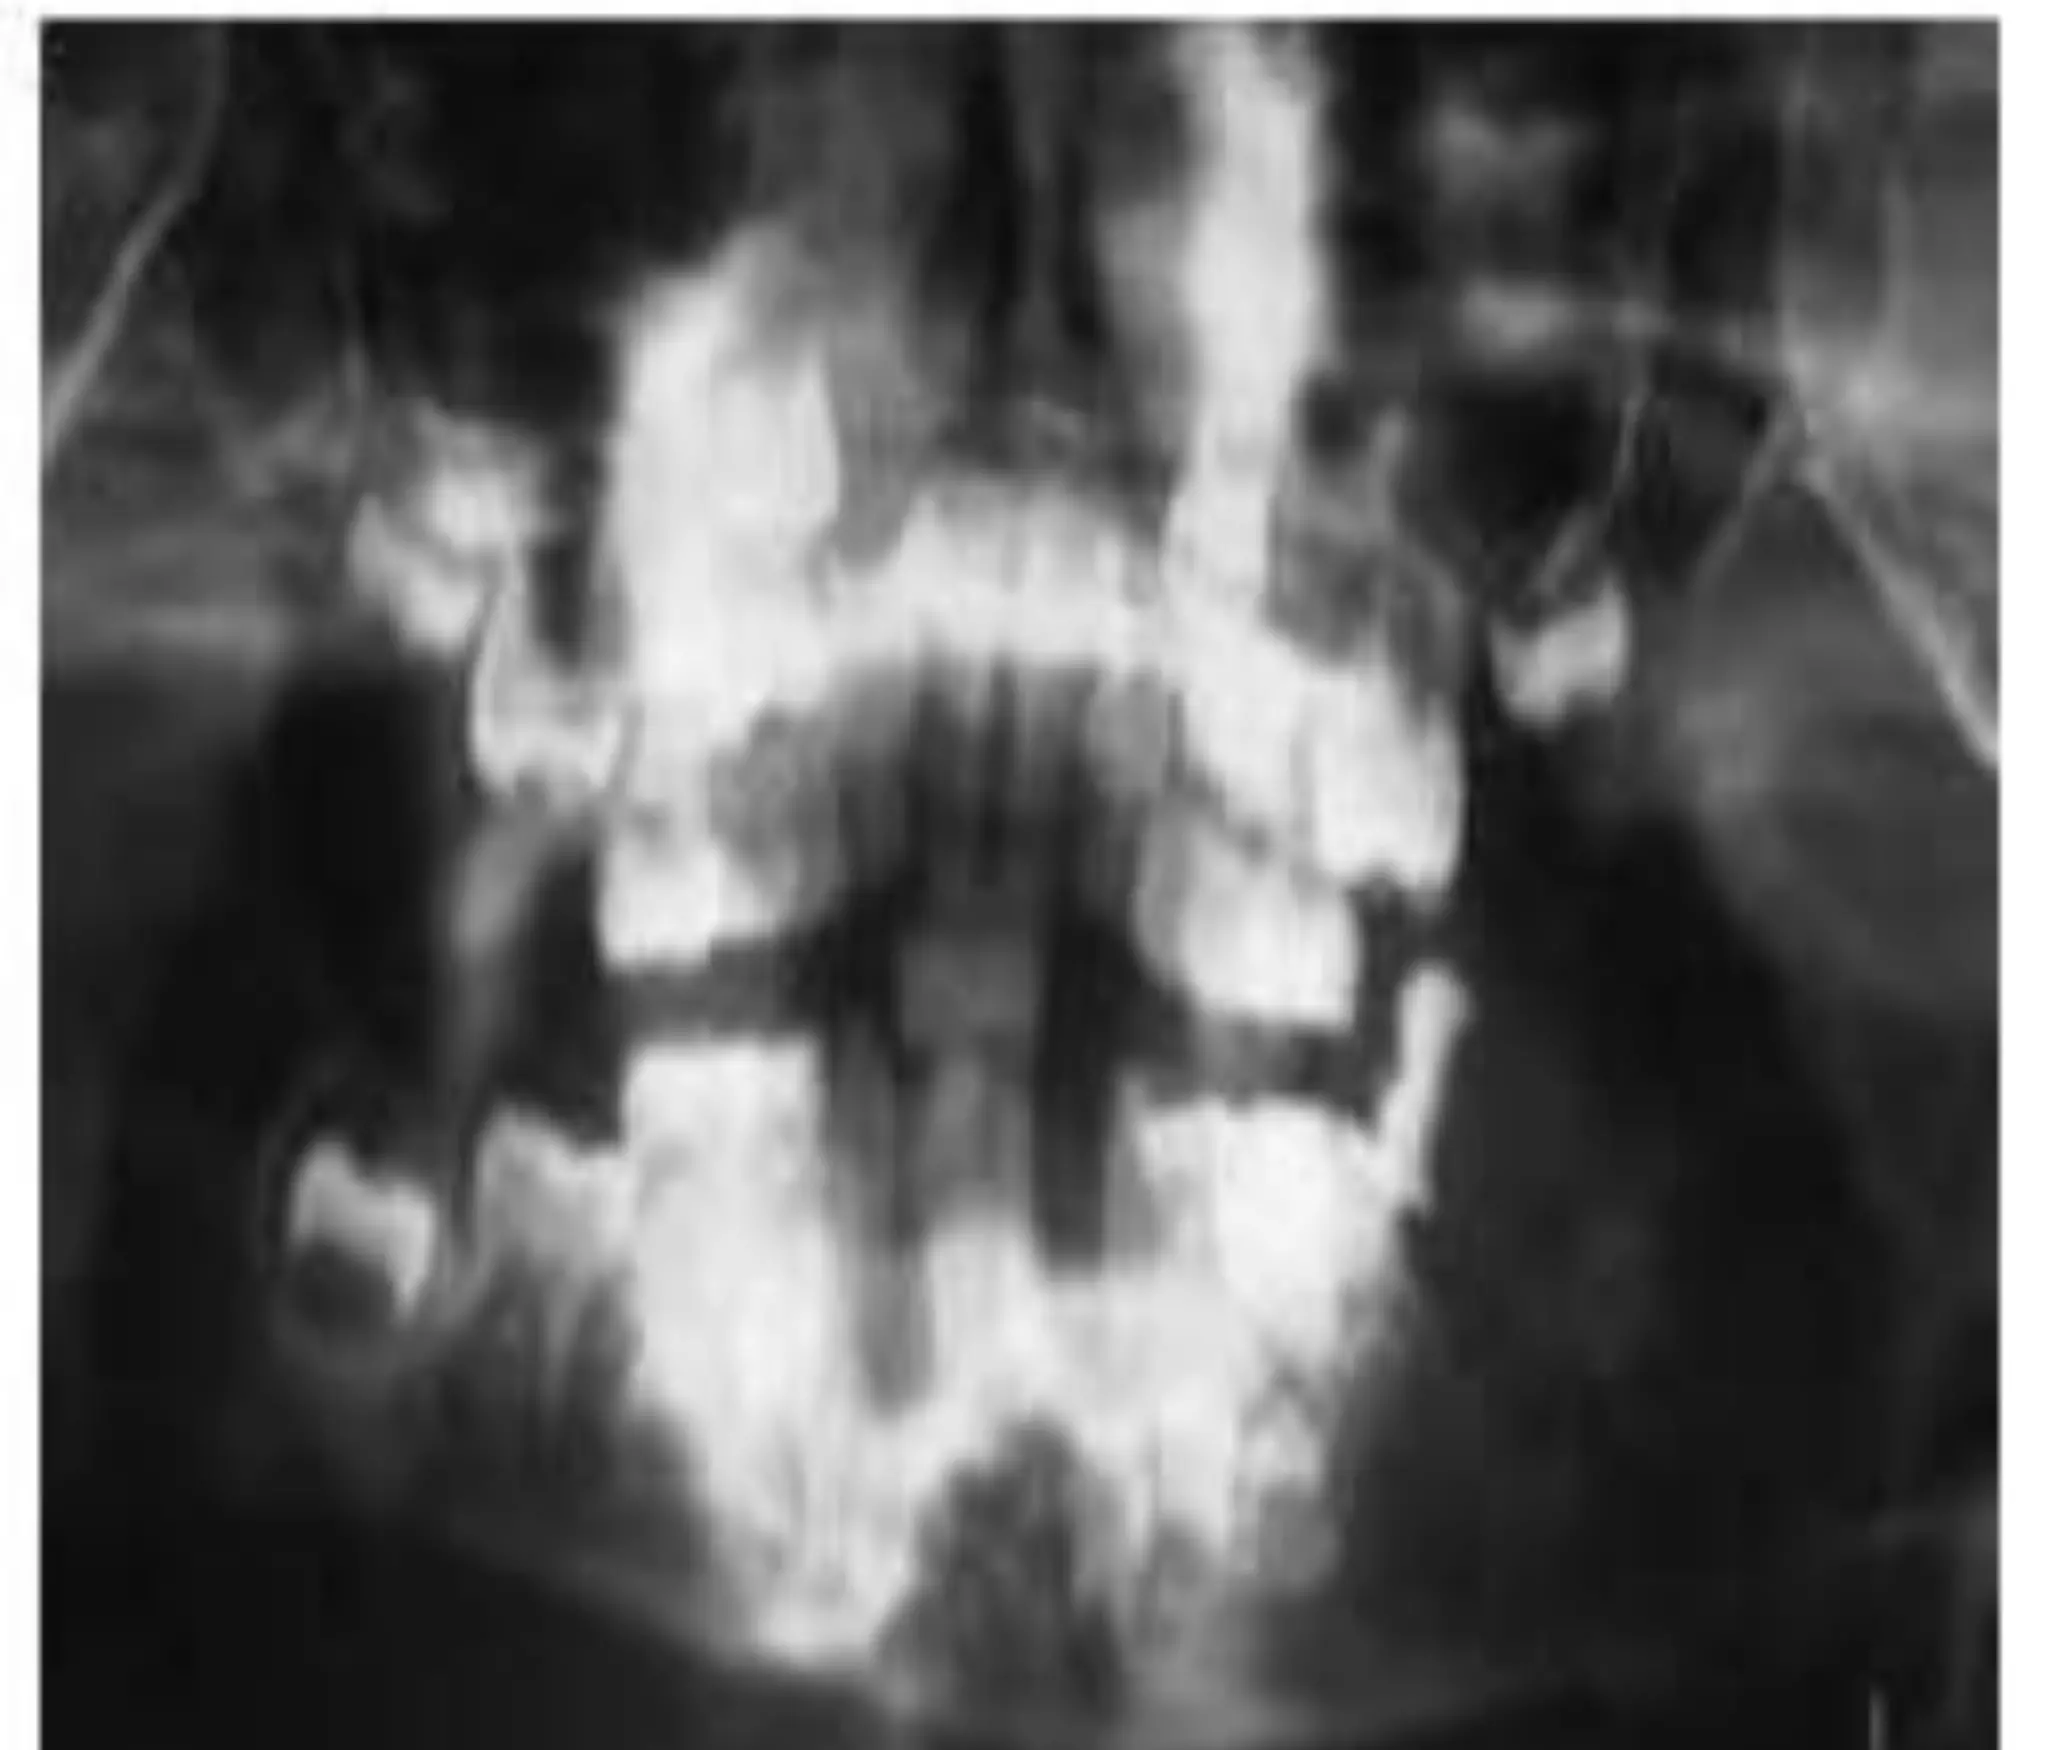

CT - PLAIN

• E/O lytic destruction involving outer horizontal

ramus,angle of the mandible wt large soft tissue

component which extend on both alveolar&buccal

aspect.

• No E/O expansion of bone/periosteal

reaction/calcification.

• E/O destruction of lamina dura &alveolar margin wt

exfoliation of teeth.

CT - PLAIN •E/O lytic destruction involving outer horizontal ramus,angle of the mandible wt large soft tissue component which extend on both alveolar&buccal aspect. • No E/O expansion of bone/periosteal reaction/calcification. • E/O destruction of lamina dura &alveolar margin wt exfoliation of teeth. 12